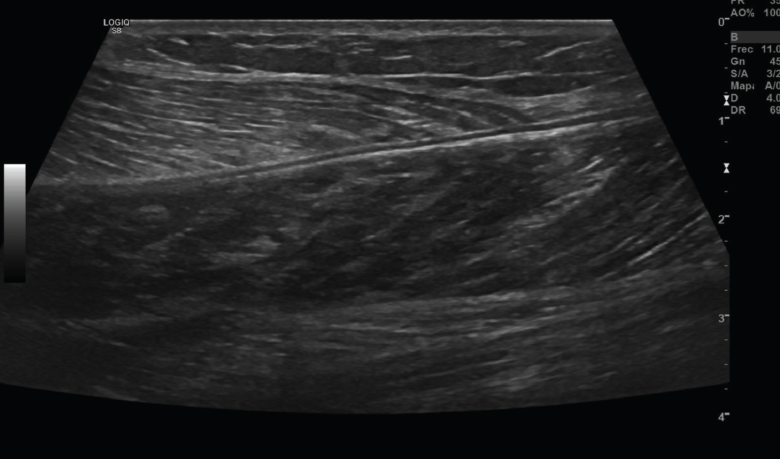

El músculo sano, ecográficamente, presenta una ecogenicidad inferior a la del tejido celular subcutáneo y una disposición de finas líneas paralelas ecogénicas, múltiples, en cortes longitudinales, en “pluma de ave”.

Se describen 4 grados de lesión muscular: grado 0, con ecografía negativa a pesar de tener clínica sugestiva; grado 1, con hiperecogenicidad en la lesión; y los grados 2 y 3, con regiones hipoecoicas por líquido adyacente a las fibras musculares. Cuando hay cicatrización, desaparece la región hipoecoica(8)(Figuras 11, 12, 13 y 14).